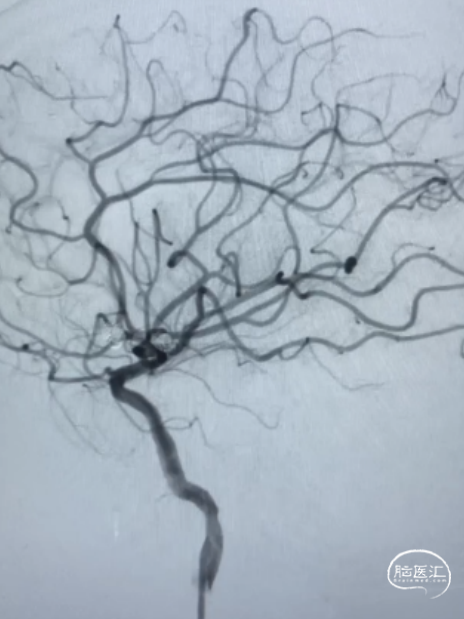

术前影像

左侧大脑中动脉M2段动脉瘤,前交通动脉瘤栓塞术后。

患者取仰卧位,麻醉成功后,行双侧腹股沟处碘伏消毒3遍,铺无菌洞巾,以Seldinger法行右腹股沟股动脉穿刺,置6F动脉鞘,以5F多功能管造影可见左侧大脑中动脉M2段动脉瘤。

术后即刻造影提示栓塞完全。